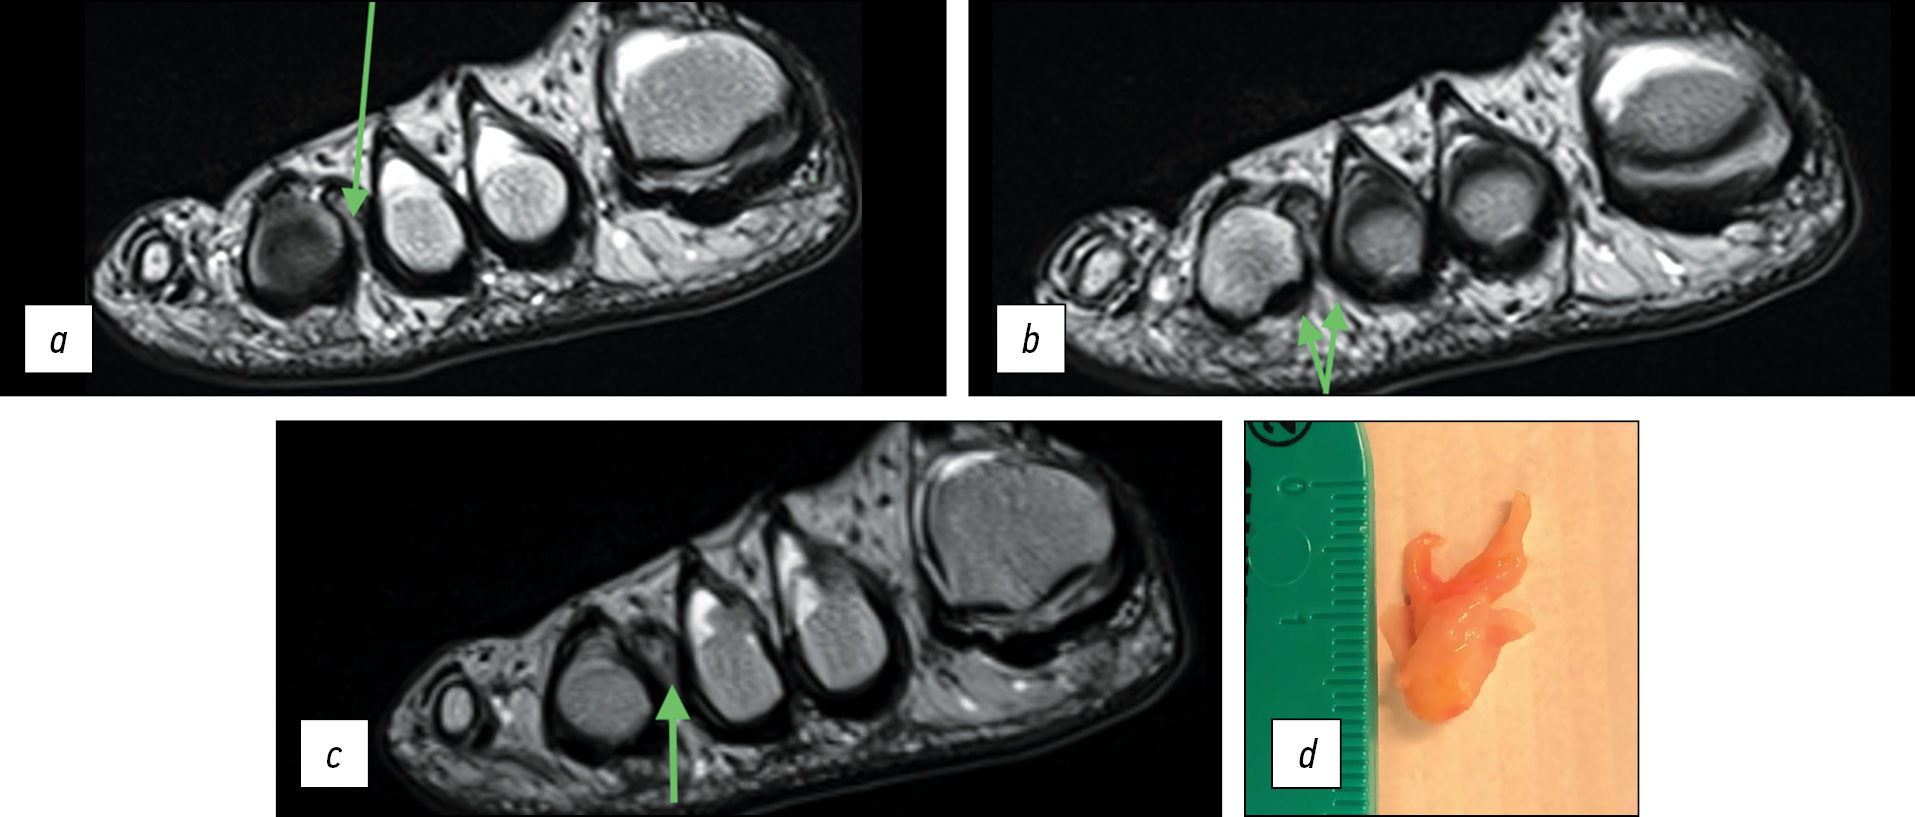

Пациент С., 49 лет. Обратился к нам в клинику с уже выполненным в сторонней клинике МРТ-исследованием. Боль в обеих стопах и парестезии с иррадиацией в третий, четвёртый и пятый пальцы беспокоили около 4 лет при высоких нагрузках на ноги (бег, альпинизм, туризм). По клинико-анамнестическим данным заподозрены невромы третьего и четвёртого межпальцевых промежутков. На предоставленной МРТ Т2-последовательность отсутствует, толщина срезов 3,5 мм. На изображениях видна неврома в третьем межплюсневом промежутке обеих стоп (только на корональных срезах), однако признаков периневрального фиброза в четвёртом межплюсневом промежутке нет (рис. 2a–d). Пациенту было предложено выполнить МРТ повторно, однако после обсуждения тактики лечения пациент предпочёл выполнить хирургическую ревизию обоих подошвенных нервов на обеих стопах. При хирургическом лечении и последующем гистологическом исследовании были обнаружены невромы третьего и четвёртого промежутков обеих стоп (рис. 2e–g).

Рис. 2. Пациент С., магнитно-резонансная томография, резецированный участок нерва, микропрепарат: a — МРТ: гипоинтенсивный сигнал по сравнению с окружающими тканями при Т1-взвешенной последовательности, правая стопа; неврома третьего межпальцевого промежутка; b, c — МРТ: неинформативные срезы в дистальном и проксимальном направлениях (толщина срезов 3,5 мм), правая стопа; Т1-взвешенная последовательность; d — МРТ: гипоинтенсивный сигнал по сравнению с окружающими тканями при Т1-взвешенной последовательности, левая стопа; неврома третьего межпальцевого промежутка; e — участок резецированного материала четвёртого межпальцевого промежутка, левая стопа (фото); f — фиброз «onion skin» (фото, микропрепарат); g — истончение кровеносных сосудов (фото, микропрепарат)

Fig. 2. Patient C., MRI imaging, resected portion of the nerve, microscopic specimen: a — MRI: hypointense signal compared to surrounding tissues with a T1-weighted sequence, right foot; neuroma of the third interdigital space; b, c — MRI: uninformative sections in the distal and proximal directions (section thickness 3.5 mm), right foot; T1-weighted sequence; d — MRI: hypointense signal compared to surrounding tissues on T1-weighted sequence, left foot; neuroma of the third interdigital space; e — area of resected material of the fourth interdigital space, left foot (photo); f — “onion skin” fibrosis (photo, microscopic specimen); g — thinning of blood vessels (photo, microscopic specimen)

На предоставленной нам МРТ из сторонней клиники отсутствует Т2-взвешенная последовательность, изображение нечёткое. Невромы в четвёртом межпальцевом промежутке не визуализируются ни в одной из последовательностей в связи с малым размером (длина 0,4 см согласно протоколу гистологического исследования). Отсутствие адекватной визуализации поражённой части нерва четвёртого межпальцевого промежутка показывает крайне низкую диагностическую ценность исследования и при сопоставлении с клинико-анамнестическими данными, требует выполнения повторной томографии.